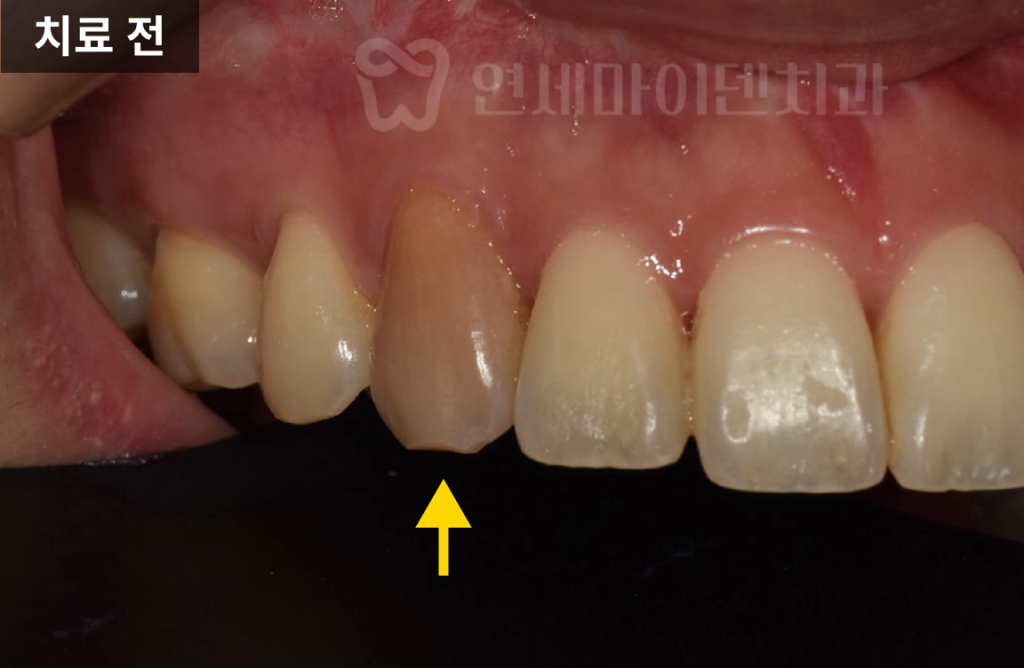

앞니 바로 옆에 위치한 치아인데 옆 치아와 색이 확연히 다른 것을 볼 수 있습니다.

실제로 보면 웃지않고 말할 때도 보이는 부위라서

일상에서 크게 미소짓지도 못하고 신경을 쓰셨다고 합니다.

치료 전후를 비교해면 치료 후에 확연히 색이 밝아진 것이 보입니다.